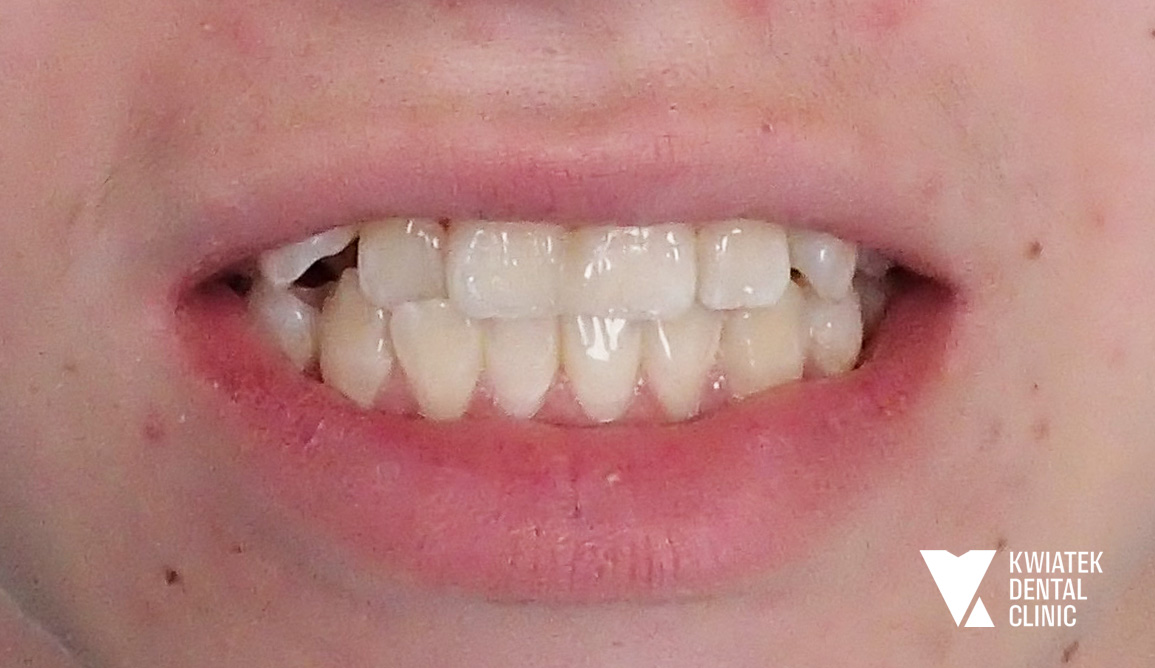

Luksus dyskretnej ortodoncji oparty na zaawansowanej technologii nakładkowej

Pacjentka zgłosiła się do kliniki z potrzebą kompleksowej poprawy zarówno funkcji zgryzu, jak i estetyki uśmiechu. W badaniu stwierdzono zgryz krzyżowy, stłoczenia zębów oraz liczne problemy wymagające leczenia zachowawczego i protetycznego, co wymagało wieloetapowego, interdyscyplinarnego podejścia. Terapię poprzedziło staranne przygotowanie jamy ustnej obejmujące ekstrakcję zębów mądrości, profesjonalną higienizację oraz odbudowę osłabionych struktur. Następnie wdrożono zaawansowane leczenie ortodontyczne z wykorzystaniem nowoczesnego systemu nakładkowego. Rezultatem jest harmonijny, stabilny zgryz, idealnie ukształtowane łuki zębowe oraz wyraźnie odmłodzony, jasny uśmiech, podkreślony profesjonalnym wybielaniem.